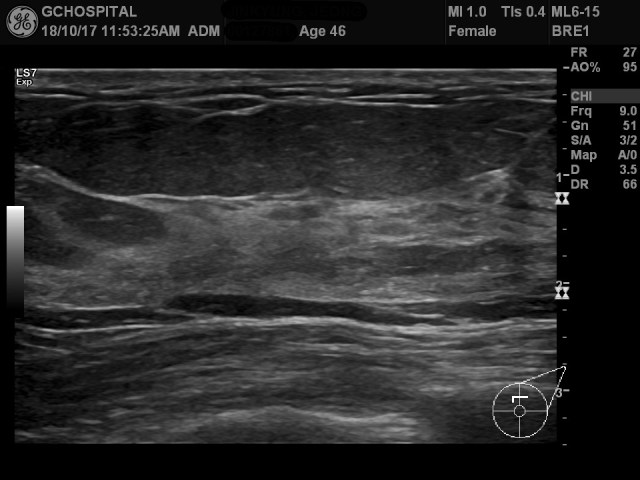

00127861_US_20181017354_20181017_001

이 영상은 같은 환자의 같은 곳을 촬영하되, dynamic range와 게인 값만 다르게 해서 얻은 영상입니다.

표층에 있는 지방조직의 음영은 굉장히 낮아져 있어서 해당부위에 작은 병변이 있더라도 놓치고 넘어가기 쉬울 정도입니다.

반면, 유방조직 내에 존재하는 세세한 구조물들과 위쪽의 영상에서는 잘 구분되지 않았던 유방조직 내부에 존재하는 지방조직(intralobular fat tissue)등이 훨씬 더 또렷하고 선명하게 대비됩니다.

게인값을 56에서 51로 낮추면서 상대적으로 에코가 높고 화면에서 밝게 보이는 유방조직을 적절한 밝기로 보여주는 것도 좋은 영상을 만드는데 공헌한 게 맞지만, 다이나믹 레인지를 좁혀서 조직 안에서의 대조도를 높인 것이 적절한 게인값이 공헌한 것보다 훨씬 많은 역할을 하고 있습니다.

이렇게 다이나믹 레인지를 좁히면, 구분하기 어려운 작은 구조물들이 더 또렷하고 선명하게 보이는 효과를 기대할 수 있습니다. 반면, 그 반대급부로는 영상에 보이는 다양한 구조물들을 전체적으로 조망하는 데는 불리할 수 밖에 없겠죠. 아래 영상에서 유방조직의 내부구조는 선명하게 보이는 반면, 지방조직은 훨씬 음영이 떨어지면서 지방조직 내부의 구조물들을 확인하는 것은 훨씬 어려워 지고 있는 것이 그 점을 잘 보여주고 있습니다.